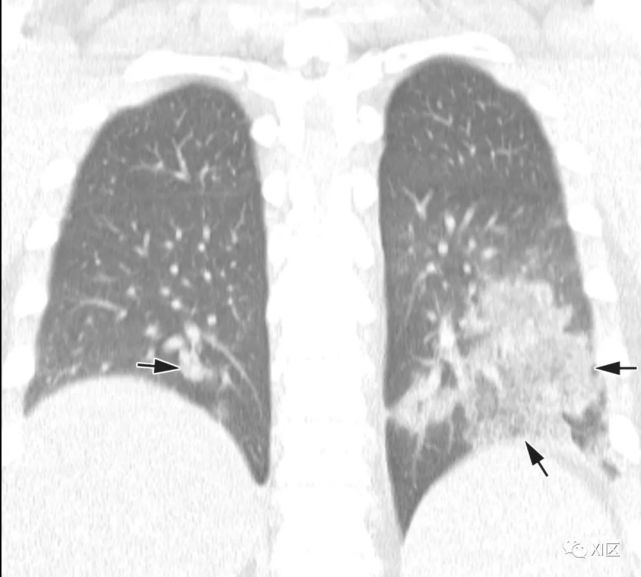

图17 50岁女性,因HMPV引起的肺炎,表现为发烧、咳嗽和咳痰。

(上) 胸片显示右肺多结节性气腔影(箭头)。在同一天获得的薄层(1mm)轴位(中)和冠状位(下)重建(5mm)的胸部CT图像显示沿支气管血管束的多个不明确的中心小叶结节(箭)或GGO(箭头),两肺轻度支气管壁增厚,尤其是右肺。